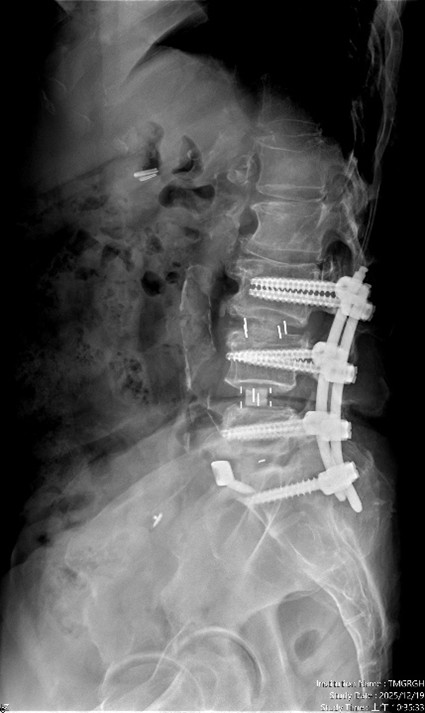

圖四、手術後除了重建椎間高度,也將腰椎的生理曲線重建為較理想的前凸狀態。